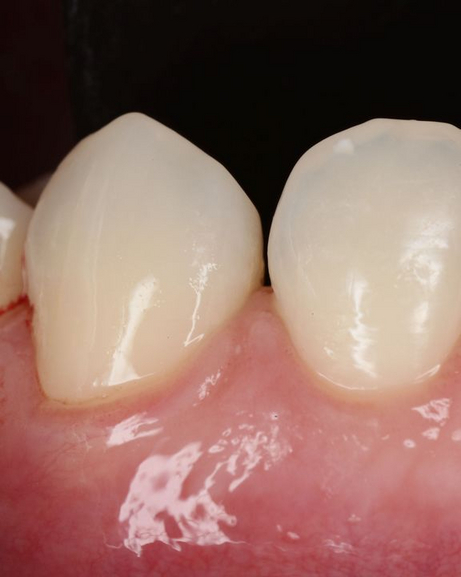

Innesti di tessuto molle possono essere utilizzati per coprire le radici esposte ma anche per ricostruire il tessuto che è andato perso. Il tessuto molle viene prelevato dal palato o da altre zone intraorali. L’intervento è quasi indolore e non esistono possibilità di rigetti. Il tessuto prelevato dalla zona donatrice si riforma spontaneamente in poche settimane.

Numerosi benefici derivano dalla chirurgia plastica parodontale: l’innesto di tessuto molle ricostruisce il tessuto perso e previene l’ulteriore progressione della recessione gengivale e dell’osso alveolare. Gli innesti gengivali riducono la sensibilità del dente e prevengono la formazione delle carie alle radici. E soprattutto migliorano l’aspetto estetico della linea gengivale e quindi del sorriso di ogni paziente.